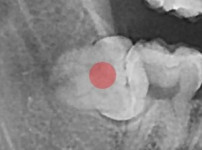

부분 매복 사랑니